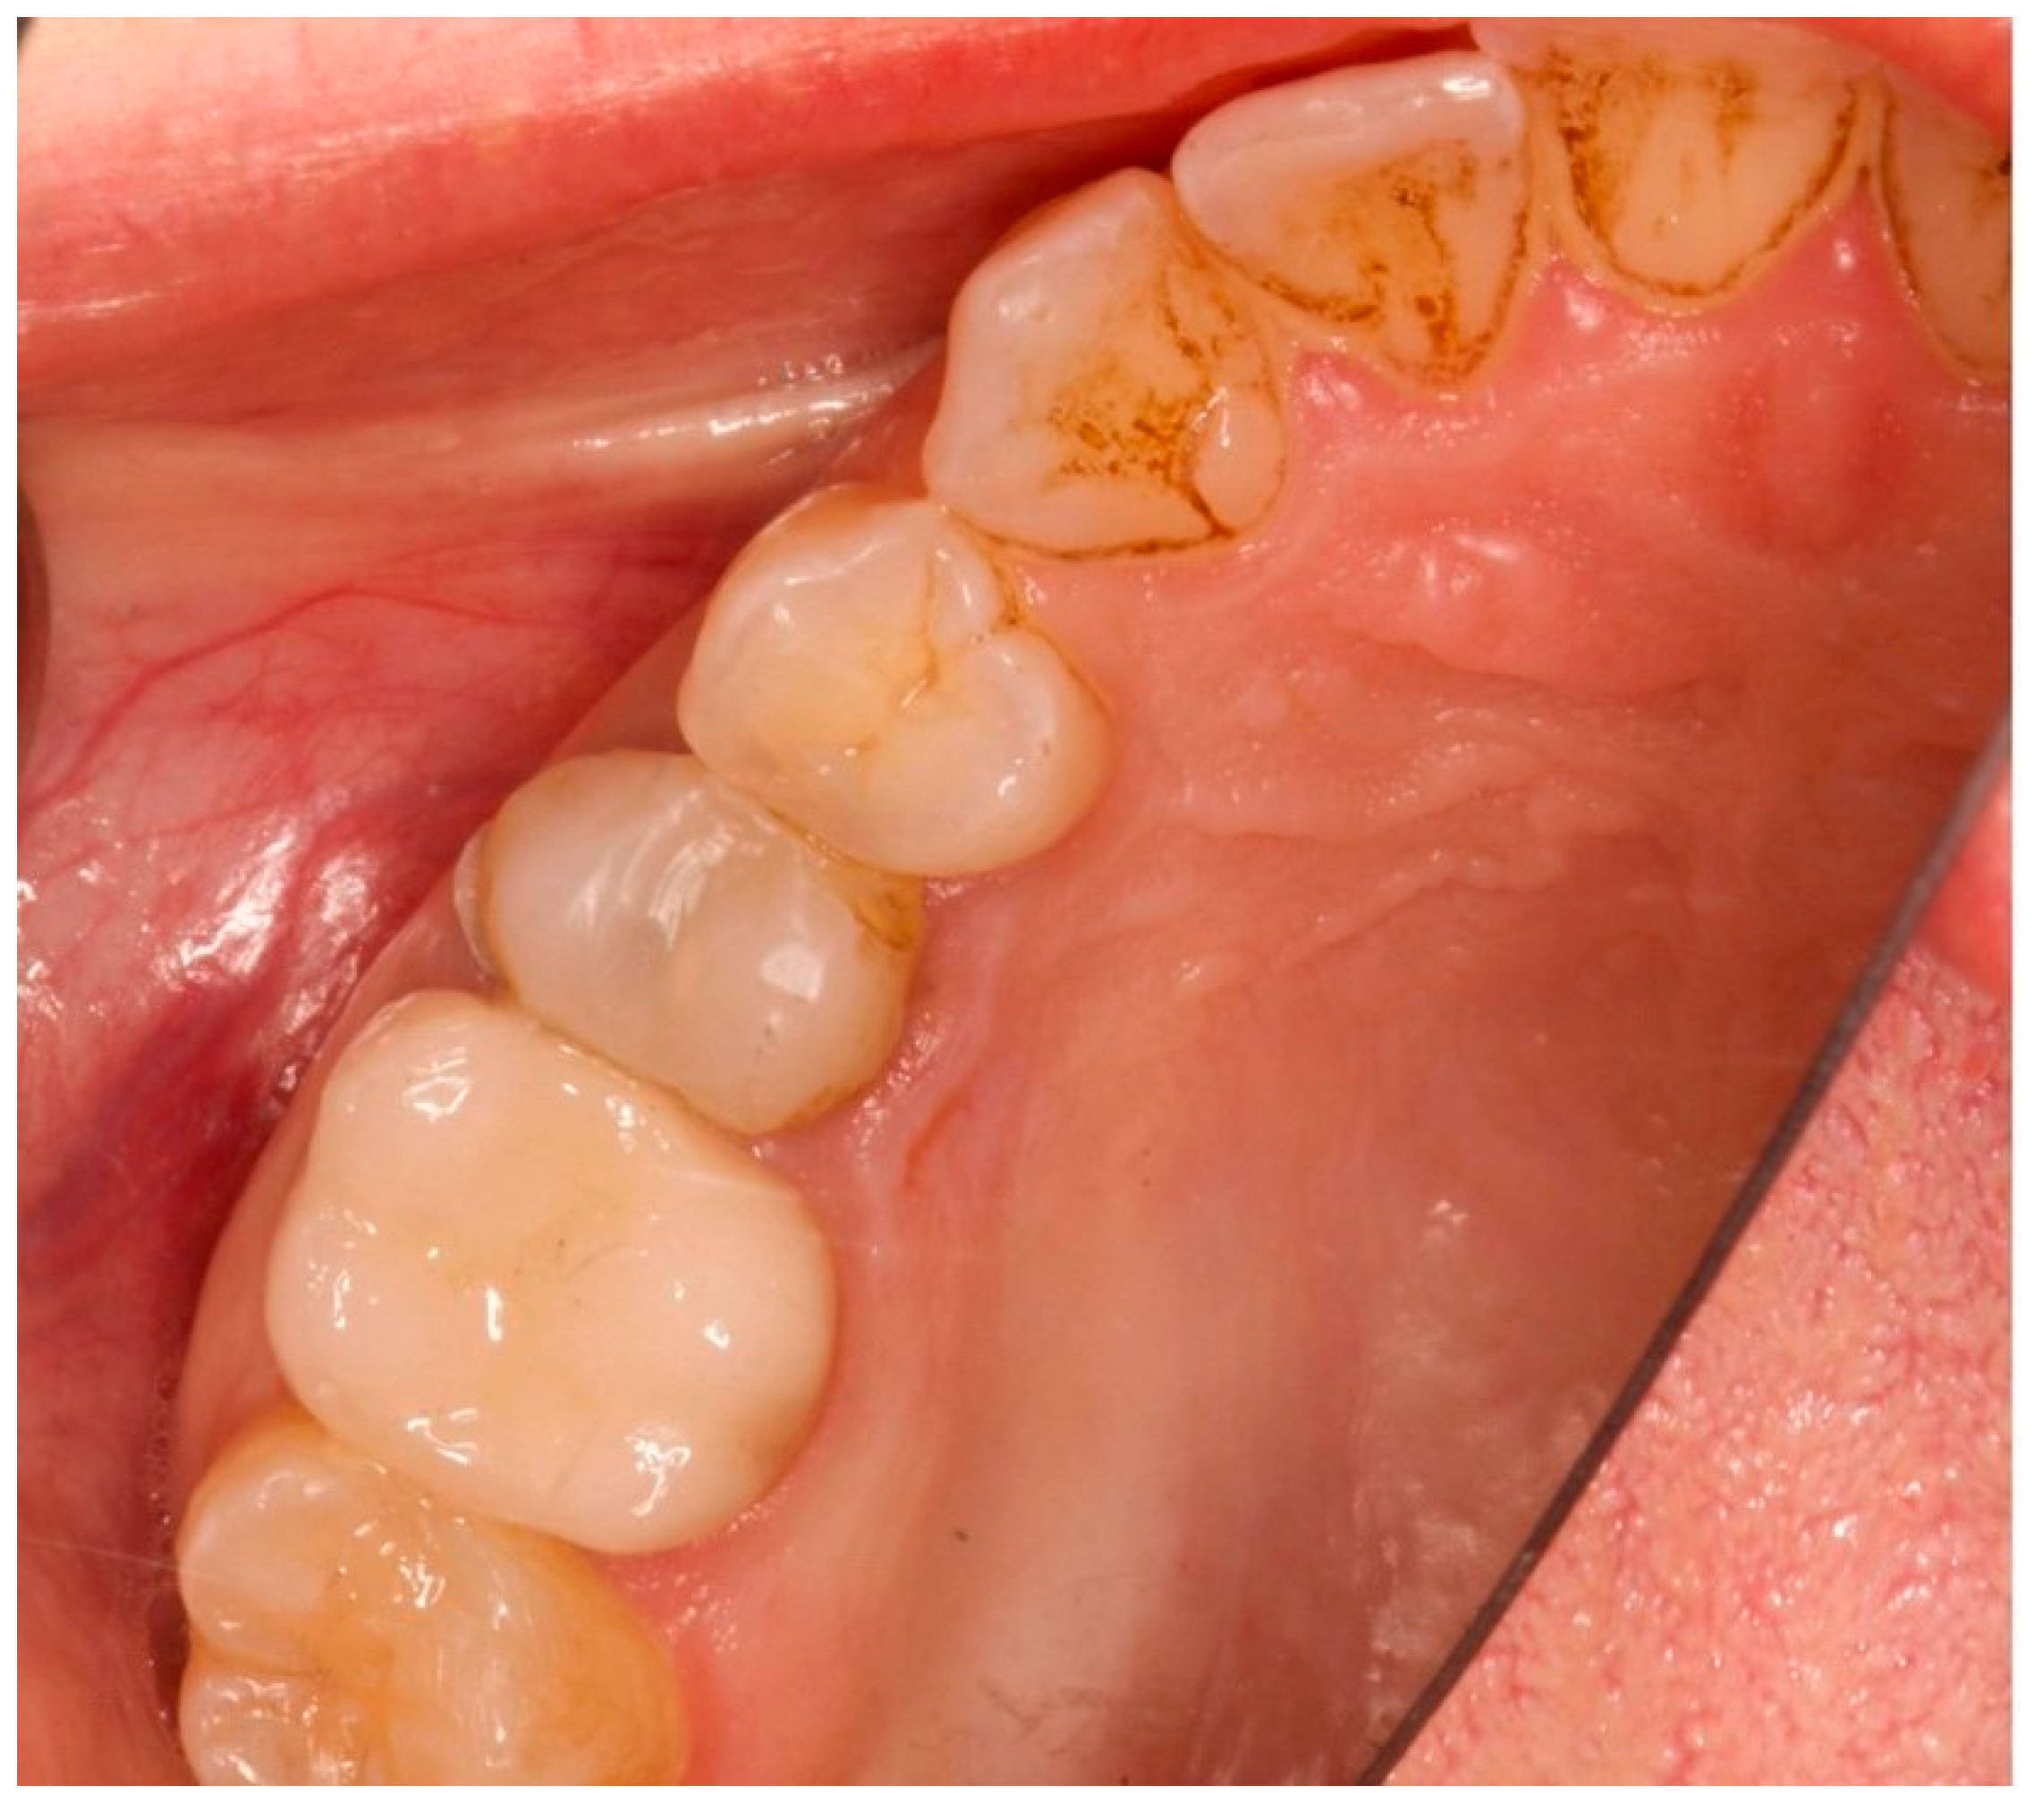

The primary outcome measure was the maintenance of peri-implant soft tissue architecture over a period of five years, assessed by measuring the distance between the peri-implant soft tissue margin (defined as the gingival and peri-implant connective tissue) and the implant fixture surface (defined as the surface of the implant that is surgically placed into the jawbone) at baseline (T0), three months (T1), one year (T2), and five years (T3). T0 represents the situation after the implant insertion. Upper premolars (teeth 1.4 and 1.5) and molars (teeth 1.6 and 1.7) designated for extraction had ≥5 mm apical bone, ≥12 mm height, ≥5.5 mm alveolar bone thickness, and D2 or D3 bone quality (Misch classification). Teeth lacking vestibular/palatal cortical bone, with periapical/periodontal lesions, or Class B/C (Tarnow classification) were excluded (Figure 1, Figure 2 and Figure 3A).

Figure 2.

Occlusal view prior to implant insertion of tooth 1.5.